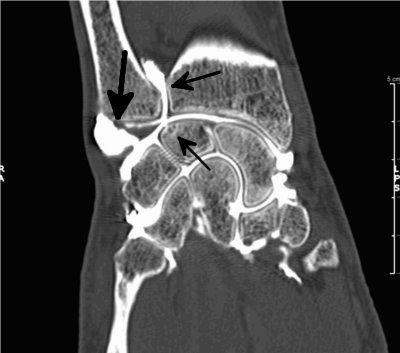

Poignet

Rupture du ligament triangulaire (flèche de droite)

Rupture des ligaments ulno-carpien et luno-pyramydal, chondropathie dégénérative (flèche du bas)